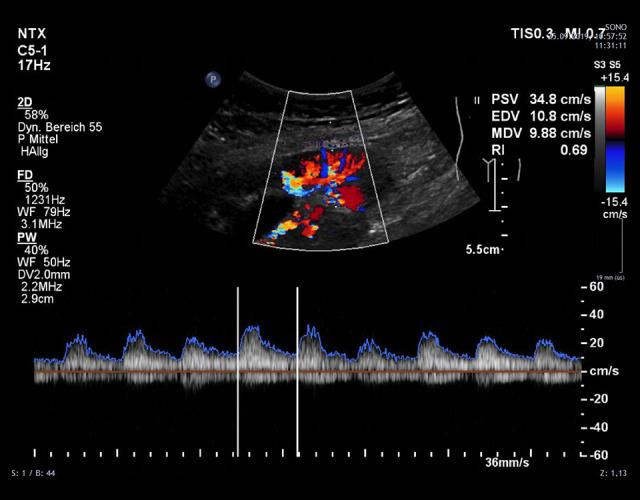

BACKGROUND There has been, to our knowledge, no reports on LifeCycle Pharma tacrolimus (LCPT) taken during pregnancy after simultaneous pancreas-kidney transplantation (SPK). Here, we report a 25-year-old female SPK recipient who gave birth to a healthy infant in posttransplant month 32. We analyzed the long-term graft function, obstetric/neonatal course, LCPT dosage, tacrolimus (TAC) levels, concomitant medication, and complications. CASE REPORT Her medical history consisted of type 1 diabetes with chronic nephropathy, arterial hypertension, and atypical haemolytic uremic syndrome with critical deterioration of her general condition requiring clinically indicated early termination of her first pregnancy prior to SPK. SPK was performed according to surgical standards. The immunosuppressive prophylaxis consisted of thymoglobulin, mycophenolate mofetil, standard TAC formulation, and steroids. Due to rapid TAC metabolism, the patient was converted from a standard TAC formulation to LCPT in the first month posttransplant. Her long-term immunosuppression, including the obstetric and peripartal course, consisted of LCPT, prednisolone, and azathioprine. She was normotensive without antihypertensive medication and maintained excellent function of both grafts during the observation period of 48 months posttransplant. All (mostly infectious) complications were reversible, especially temporary polyoma viremia within normal renal function, and 2 episodes of urosepsis. No relapse of her pretransplant episode of atypical haemolytic uremic syndrome occurred posttransplant. Her child is in good health at the age of 12 months without any malformations. CONCLUSIONS This case suggests that pregnancy after SPK under LCPT is feasible. Further studies are needed to expand the empirical knowledge surrounding tacrolimus.